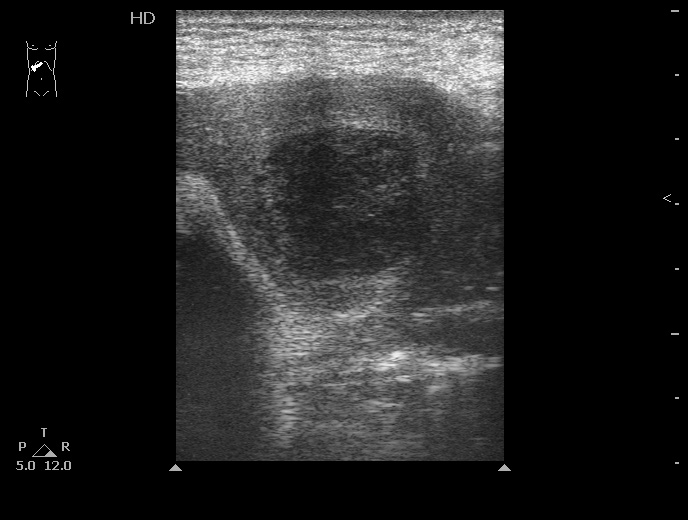

06-12-05-105726_KAZACHENKO-.jpg

06-12-05-105726_KAZACHENKO-.jpg (49.5 КБ) 1448 просмотров

Типичная картина ##1-4:

Гипоэхогенное неоднородное округлое образование, окруженное эхогенным "демаркационным валом"

измененной паренхимы печени.